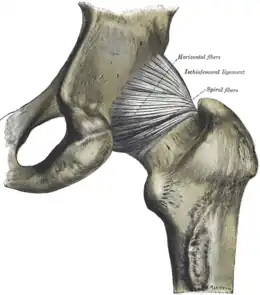

La capsule est renforcée par trois ligament extra-articulaire :

- le ligament ilio-fémoral, antérieur, qui unit l'épine iliaque antérieure et inférieure au petit et au grand trochanter en se dédoublant en deux faisceaux en Y inversé,

- le ligament pubo-fémoral, antérieur et inférieur, qui relie la branche supérieure du pubis à la ligne inter-trochantérique.

- le ligament ischio-fémoral, postérieur, qui relie la partie supérieure de la tubérosité ischiatique à la crête inter-trochantérique.